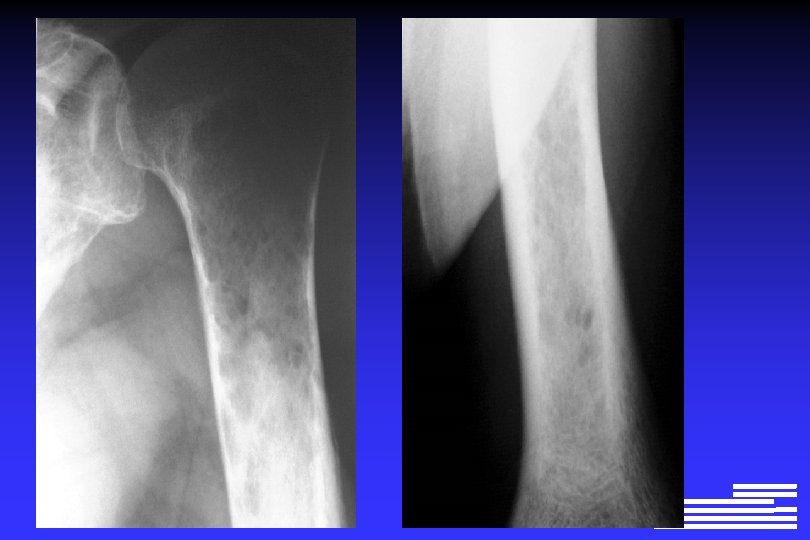

Explorations à effectuer pour le diagnostic positif et différentiel l Radiographie du squelette complet Ø Lésions lytiques à l’emporte-pièce Ø Lésions « ostéoporose diffuse » Ø Lésions condensantes (rares +++ !, 0, 5 à 3% des cas)